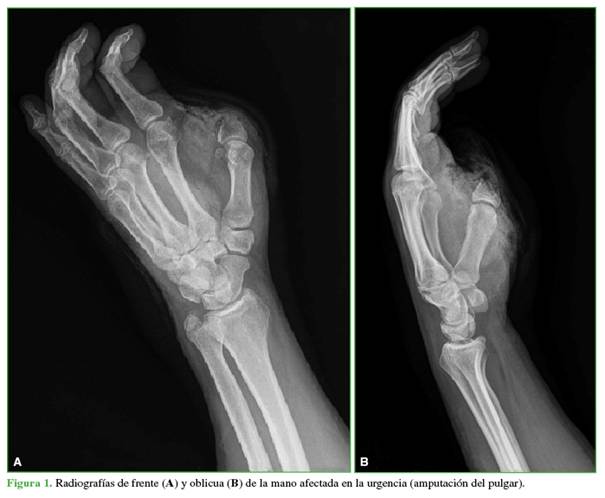

Hombre de 58 años, farmacéutico, que tenía una amputación traumática del pulgar a nivel metacarpofalángico, con un intento fallido de reimplante, en su mano dominante. Ante su negativa a la reconstrucción mediante la transferencia de un dedo del pie a la mano, se planteó la reconstrucción osteoplástica (Figura 1).